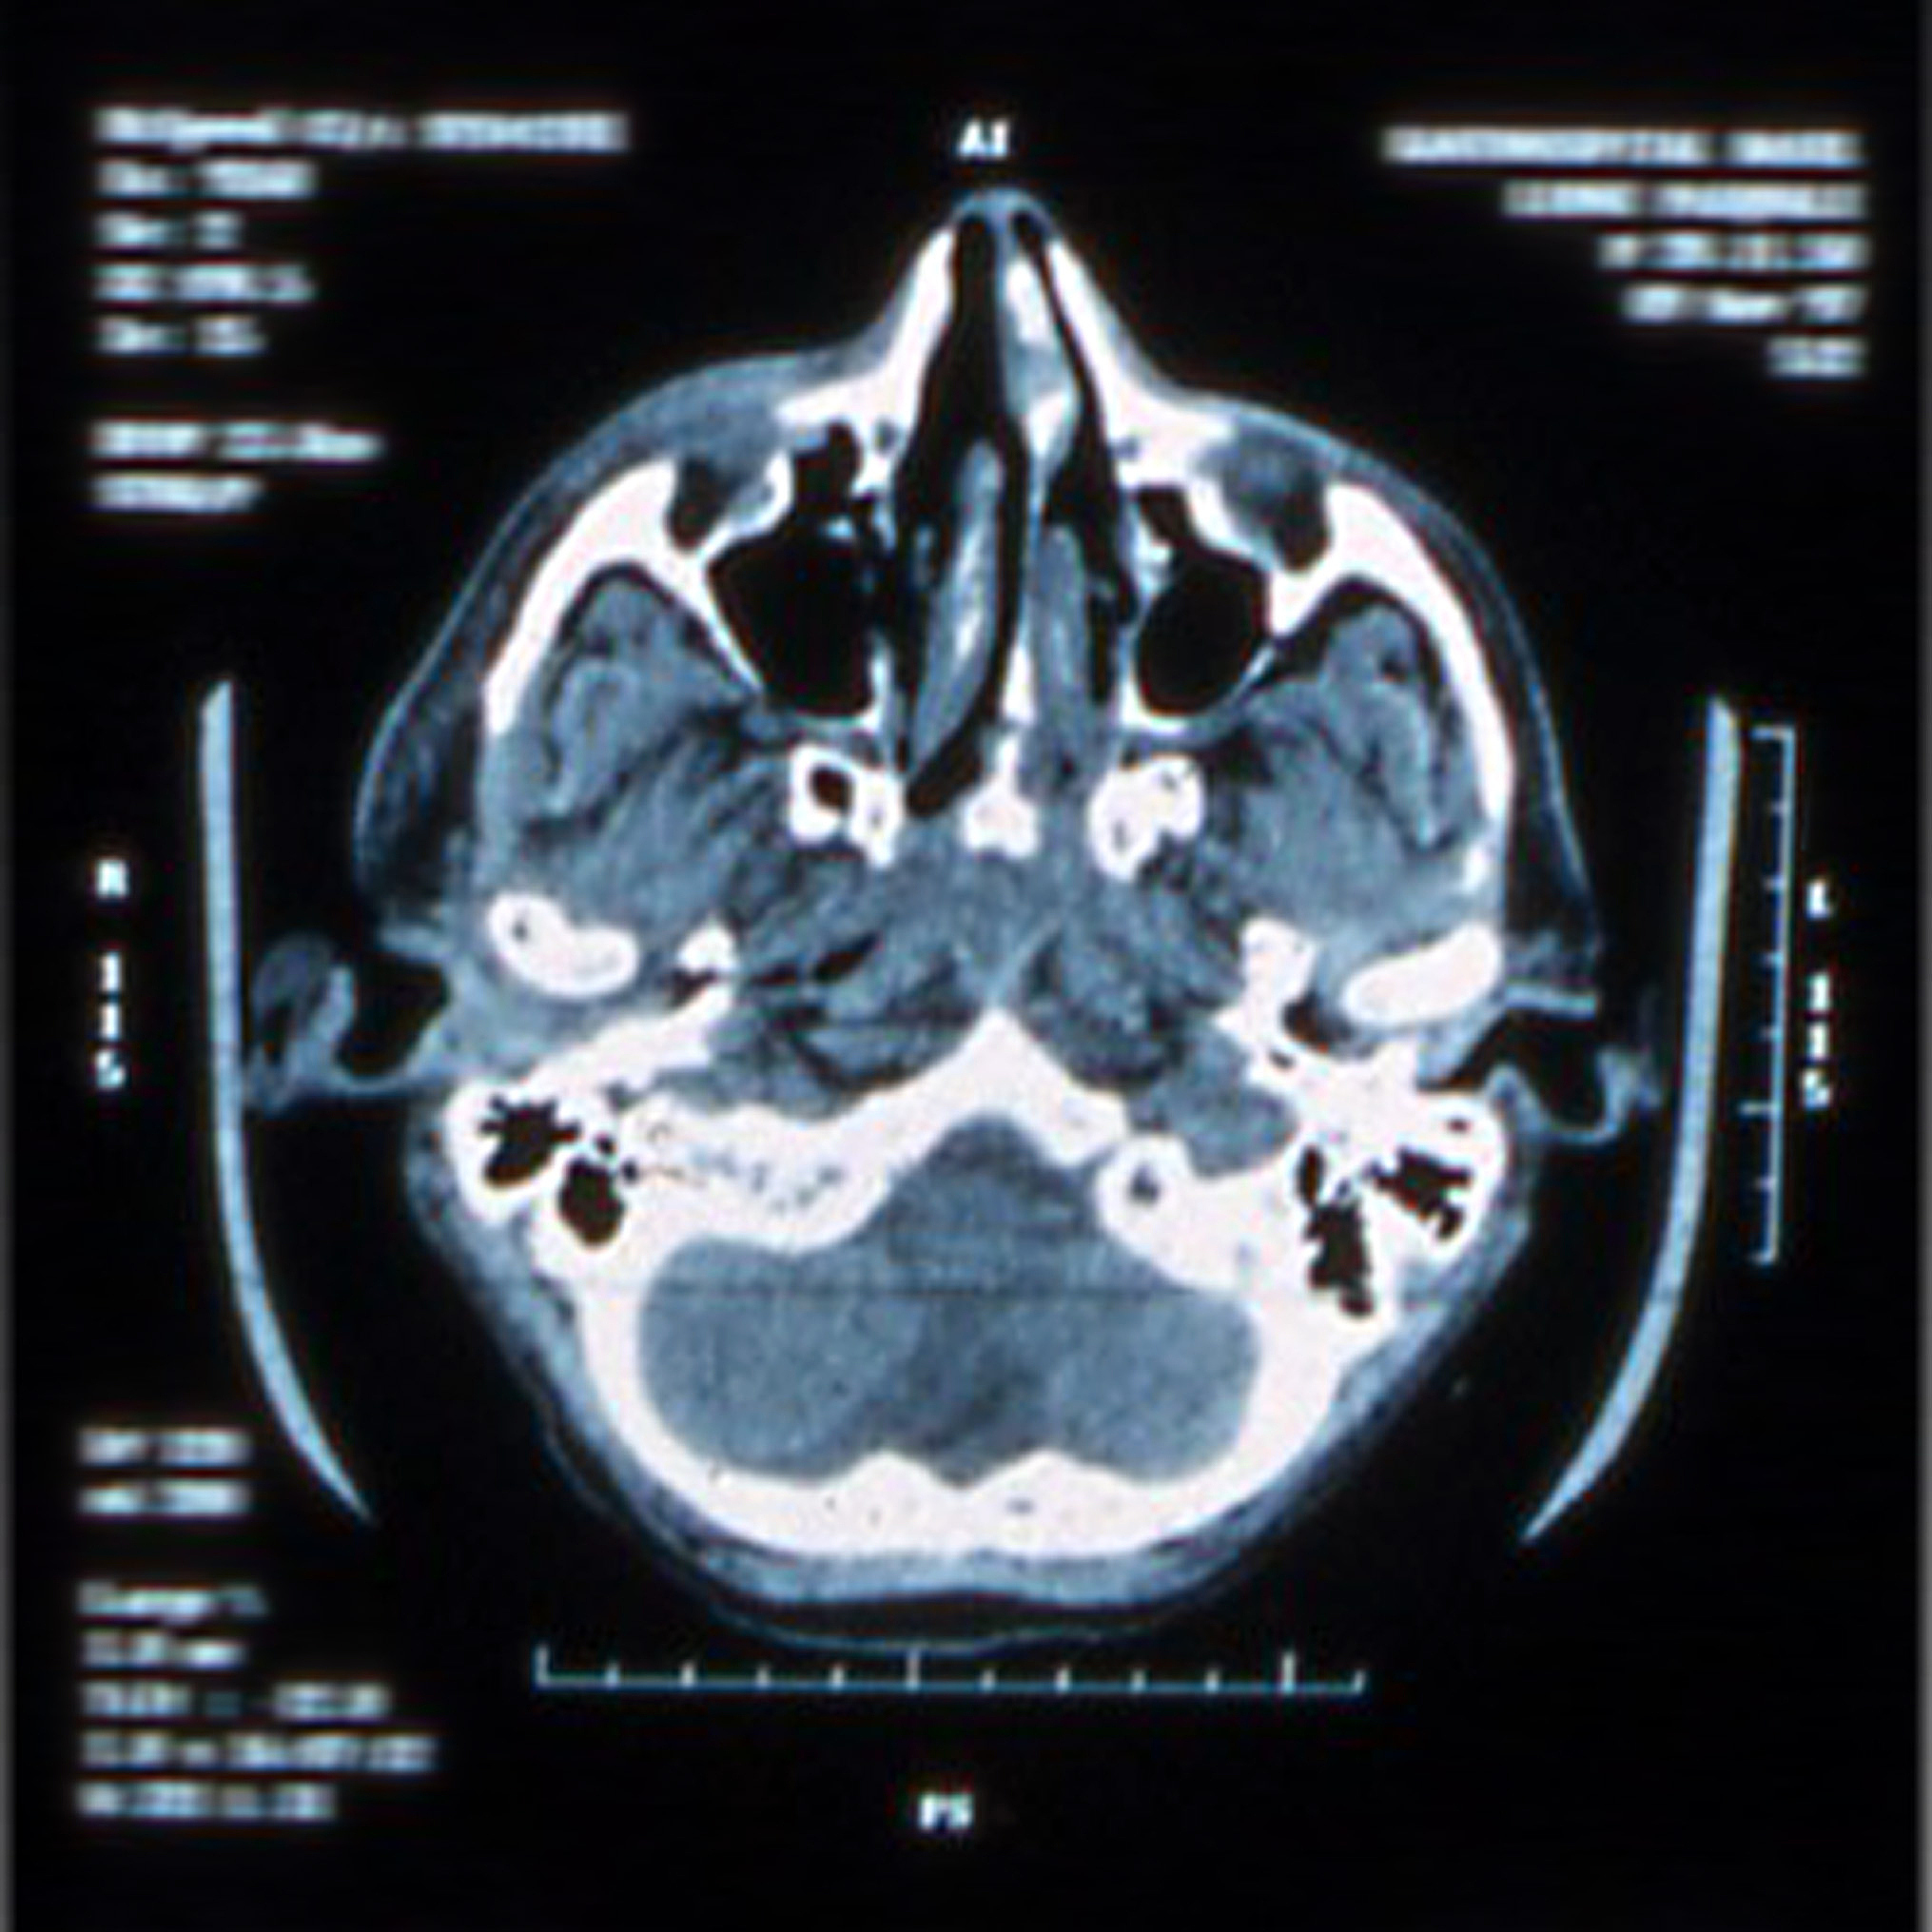

右肺小结节、右肺上叶密度增高、肺动脉旁结节、肝脏低密度影CT检查分析

\u57fa\u4e8eCT\u68c0\u67e5\u7ed3\u679c\uff0c\u5b58\u5728\u4ee5\u4e0b\u95ee\u9898\uff1a\n\n1. \u53f3\u80ba\u4e0b\u53f6\u80f8\u819c\u4e0b\u7684\u5c0f\u7ed3\u8282\u5f71\uff1a\u8be5\u7ed3\u8282\u5f71\u7684\u5927\u5c0f\u4e3a5mm\uff0c\u754c\u9650\u6e05\u6670\uff0c\u9700\u8981\u8fdb\u4e00\u6b65\u89c2\u5bdf\u5176\u6027\u8d28\uff0c\u4ee5\u786e\u5b9a\u662f\u5426\u9700\u8981\u8fdb\u4e00\u6b65\u68c0\u67e5\u6216\u6cbb\u7597\u3002\n\n2. \u53f3\u80ba\u4e0a\u53f6\u7684\u5bc6\u5ea6\u589e\u9ad8\u5f71\uff1a\u8be5\u5f71\u50cf\u8868\u73b0\u4e3a\u6591\u70b9\u72b6\u3001\u7f29\u6761\u72b6\u548c\u6591\u7247\u72b6\u7684\u5bc6\u5ea6\u589e\u9ad8\uff0c\u90e8\u5206\u75c5\u5904\u89c1\u78f7\u5316\uff0c\u754c\u9650\u8f83\u6e05\u6670\u3002\u8fd9\u4e9b\u75c5\u5904\u53ef\u80fd\u662f\u80ba\u90e8\u75c5\u7597\u7684\u5f71\u8c61\uff0c\u53ef\u80fd\u9700\u8981\u8fdb\u884c\u8fdb\u4e00\u6b65\u7684\u8bc4\u4f30\u548c\u8bca\u65ad\u3002\n\n3. \u80ba\u52a8\u8109\u65c1\u7684\u4f4e\u5bc6\u5ea6\u7ed3\u8282\u5f71\uff1a\u8be5\u7ed3\u8282\u5f71\u7684\u5927\u5c0f\u7ea6\u4e3a15mm\uff0c\u754c\u9650\u6e05\u6670\u3002\u8fd9\u4e2a\u7ed3\u8282\u5f71\u53ef\u80fd\u9700\u8981\u8fdb\u4e00\u6b65\u8bc4\u4f30\uff0c\u4ee5\u786e\u5b9a\u5176\u6027\u8d28\u548c\u662f\u5426\u9700\u8981\u8fdb\u4e00\u6b65\u5904\u7406\u3002\n\n4. \u80be\u810f\u7684\u4f4e\u5bc6\u5ea6\u5f71\u50cf\uff1a\u6d4b\u653e\u4e2d\u53d1\u73b0\u80be\u810f\u7684\u7c7b\u5706\u5f62\u4f4e\u5bc6\u5ea6\u5f71\u50cf\uff0c\u754c\u9650\u4e00\u5f80\u6e05\u6670\u3002\u52a0\u4e4b\uff0c\u53f3\u80be\u53f6\u8fd8\u53ef\u89c1\u4e00\u4e2a\u7a00\u4f4e\u5bc6\u5ea6\u7684\u4e0d\u89c4\u5219\u5f71\u50cf\uff0c\u76f8\u5f84\u7ea6\u4e3a26mm\u3002\u8fd9\u4e9b\u5f71\u50cf\u53ef\u80fd\u8868\u793a\u80be\u810f\u75c5\u53d8\uff0c\u9700\u8981\u8fdb\u4e00\u6b65\u8bc4\u4f30\u548c\u8bca\u65ad\u3002\n\n\u9700\u8981\u7ed3\u5408\u4e3b\u89c2\u75c5\u53f2\u548c\u5176\u4ed6\u68c0\u67e5\u7ed3\u679c\uff0c\u5982\u8840\u6db2\u68c0\u67e5\u3001\u80bf\u7624\u6807\u5fd7\u7269\u7b49\uff0c\u8fdb\u884c\u7efc\u5408\u5206\u6790\u548c\u8bca\u65ad\uff0c\u4ee5\u786e\u5b9a\u75c5\u53d8\u7684\u6027\u8d28\u548c\u8fdb\u4e00\u6b65\u6cbb\u7597\u65b9\u6848\u3002\u5efa\u8bae\u54a8\u8be2\u4e13\u4e1a\u533b\u751f\u6216\u80ba\u90e8\uff0f\u80be\u810f\u75c5\u7597\u4e13\u79d1\u533b\u751f\uff0c\u4ee5\u83b7\u5f97\u51c6\u786e\u7684\u8bca\u65ad\u548c\u6cbb\u7597\u5efa\u8bae\u3002